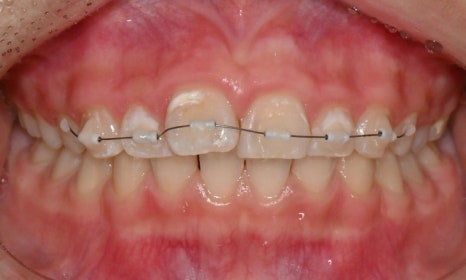

첫번째 세트 마무리 후

총 7개의 인비절라인 장치로 튀어나온 오른쪽 두번째 앞니를 배열하고 벌어진 앞니 사이 공간을 타이트하게 닫아주었습니다. 7개 장치가 마무리된 이후 아직 살짝 두번째 앞니가 아래 앞니와 닿는 느낌이 든다고 하여 추가교정장치(additional agligners)를 제작하기로 하였습니다.

총 7개 장치의 치료과정이 마무리 된 후 새로운 클린체크 치료계획을 세워서 마무리가 덜 된 부분을 조금 더 치료하는 과정으로, 본 환자의 경우 앞니 각도를 조금 더 조절해주며 전체적으로 위 앞니를 위로 올려주어 과개교합을 개선하여 앞니끼리 닿지 않도록 하였습니다.